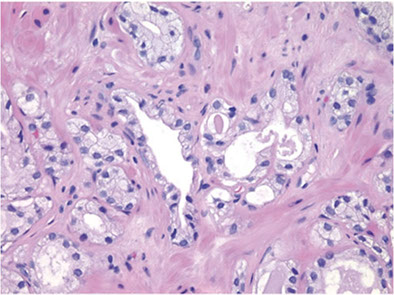

Sclerosing Adenosis (SA)

- used to be called adenomatoid prostate tumor

May be in up to 2% of prostates

- usually seen in TURP specimens for obstruction

- usually only 1 or 2 small foci are present, though can be many

- as in any TURP specimen, cannot distinguish multifocality or multiple sections through single lesion

- must diff from AC

- sclerosing adenosis has mix of well-formed glands, single cells and cellular spindle cell component

To prevent misdiagnosis of malig:

1) AC usually is an extensive process, finding only a small region should lead you to consider sclerosing adenosis or paraganglia

- although sclerosing adenosis is usually well-circumscribed, may be minimally infiltrative at perimeter

2) Glands in sclerosing adenosis resemble those of ordinary adenosis, and are made of cells c pale to clear cytoplasm, and b9-appearing nuclei

- many of the glands have visible basal cells

3) SA has dense spindle cell component not seen in AC, stromal cells plump fusiform cells c amphophilic cytoplasm; stroma has myxoid appearance

- AC usually does not have stromal response or at most a hypocellular fibrotic rxn

4) Has hyaline sheath-like structure around some of the glands

- the glands in AC lack such a collarette and have a "naked" appearance as they infiltrate the stroma

5) the bland cytology of SA helps distinguish from AC, though some glands in SA can be moderately enlarged and have prominent nucleoli

IHC:- S-100 + basal cells